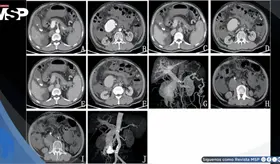

A pesar del tratamiento intervencionista exitoso mediante embolización, evolucionó con complicaciones de hipertensión portal severa, presentando descompensación aguda con hemorragia digestiva alta y choque hipovolémico.